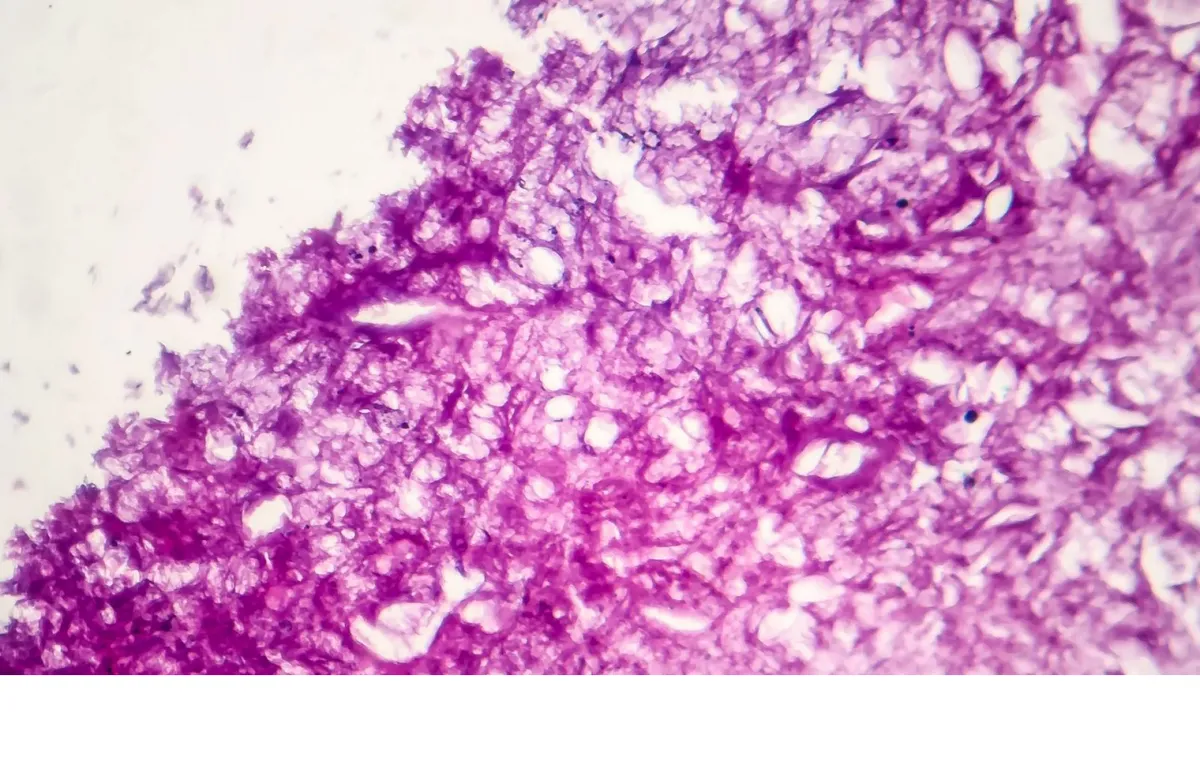

نابودی ۹۹ درصدی سلول‌های سرطانی ممکن شد

دانشمندان توانستند با استفاده از تکنیک «مولکول‌های ارتعاشی» بتوانند به مشکل مقاوم شدن سلول‌های سرطانی در مقابل داروهای شیمیایی موجود که درمان این بیماری را با دشواری مواجه می‌کند، پایان دهند.

به گزارش گروه سلامت خبرگزاری علم و فناوری آنا، دانشمندان در مراحل اولیه تحقیقات خود در مورد تکنیک «مولکول‌های ارتعاشی» موفق شدند ۹۹ درصد از سلول‌های ملانوما را که نوعی از سرطان پوست است، در آزمایشگاه ریشه کن کردند.

ایجاد ارتعاش در مولکول‌ها در این روش با استفاده از نور مادون قرمز انجام می‌شود. محققان دریافتند که این روشِ تحریک مولکول‌ها در برابر کشت‌های آزمایشگاهی سلول‌های ملانوم موثر است.

در پی استفاده از این روش، چیزی به نام پلاسمون شکل می‌گیرد که به مثابه نوسان سریع الکترون‌ها در مولکول همانند عقب و جلو رفتن امواج دریا است. این پدیده باعث می‌شود که غشای سلول‌های سرطانی پاره شود.

سیسرون آیالا-اورزکو، محقق دانشگاه رایس در ایالات متحده و نویسنده اصلی نتایج این پژوهش، گفت: «ارتعاش فعال شده توسط نور نزدیک به مادون قرمز هر چیزی را که توسط مولکول احاطه شده باشد که در این مورد، سلول سرطانی است، نابود می‌کند.»

دانشمندان امیدوارند که با استفاده از این روش بتوانند به مشکل مقاوم شدن سلول‌های سرطانی در مقابل داروهای شیمیایی موجود که درمان این بیماری را با دشواری مواجه می‌کند، پایان دهند.